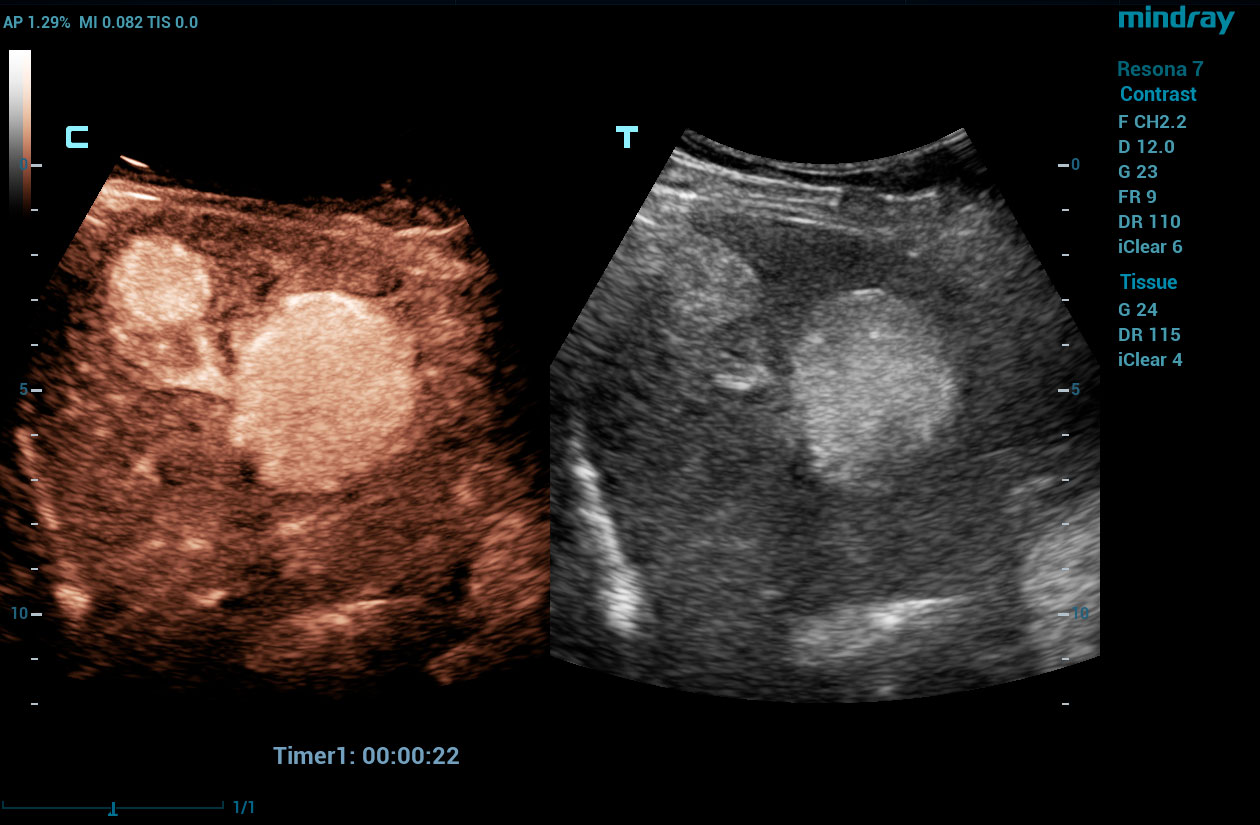

To address the changing needs of today’s value-based care environment, the Resona 7 Ultrasound System Platinum Edition was developed to capture clear, uniform images for radiology, vascular, women’s health, pediatric, and shared service imaging applications.

Premium imaging coupled with advanced workflow technologies help ease clinicians’ increasing workload by offering intuitive and easy-to-use smart tools and AI-enhanced technologies to elevate clinician and patient satisfaction. The user-directed ergonomic design is ideal for daily use, enabling clinicians to capture premium images without sacrificing comfort.

HD Scope is an advanced B-mode image processing technique that focuses additional imaging resources within a specified region of interest (ROI), analyzes the received channel data in unique ways, and applies various filtering and processing algorithms. This results in enhanced contrast resolution within the ROI based on the acoustic characteristics of varying tissue types.